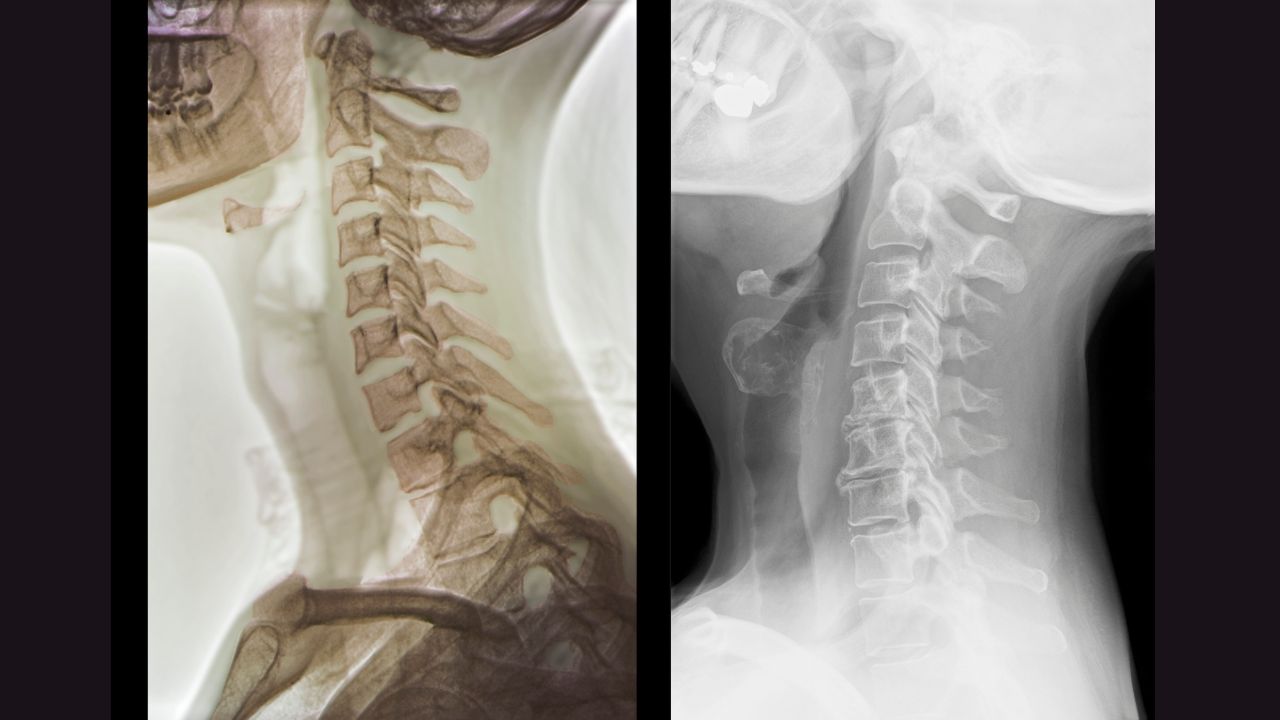

To understand cervical spondylosis better, let's delve into the anatomy of the cervical spine. The cervical spine consists of seven vertebrae, labeled C1 through C7, which are stacked on top of each other, forming the neck. Between each vertebra are intervertebral discs, which act as cushions and allow for flexibility in the spine. Surrounding the vertebrae are muscles, ligaments, and nerves that provide support and facilitate movement.

If you suspect you may have cervical spondylosis, there are several functional tests that your chiropractor may perform to assess your condition. These tests may include range of motion assessments, muscle strength testing, and neurological examinations to evaluate any weakness, numbness, or tingling in your arms or hands. Additionally, imaging tests such as X-rays or MRI scans may be ordered to visualize the extent of degeneration in your cervical spine.